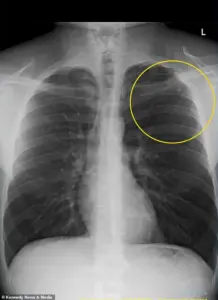

An x-ray scan revealed that his left lung had collapsed by 10 percent, a minor collapse by medical standards, but one that required immediate intervention.